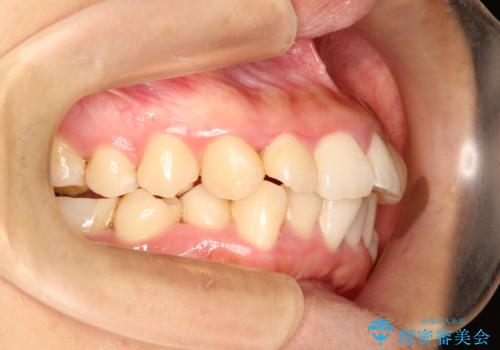

上下の歯のガタガタ ワイヤーでの抜歯矯正で整った歯並びへ

- 上下の歯のガタガタを治したいとのことで来院されました。

がたつきの度合いが強いのと、口元をなるべく引っ込めたい希望がありましたので、ワイヤーでの抜歯矯正となりました。

ガタガタが重度の方は抜歯が必要となることが多いです。

抜歯スペースを使って前歯を引っ込めることにより、口元の突出感も改善できました。